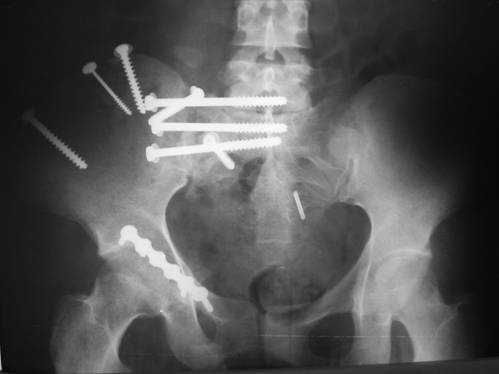

Дорогой Андрей. Мы имеем дело с комбинированной (ротационно и вертикально) нестабильностью таза со смещением правого гнемипелвиса. При таких переломах, фиксация только переднего полукольца вне зависимости от метода фиксации, как уже было сказано Djoldas Kuldjanov, M.D., не может создать адекватной фиксации. И перелом пластины был вполне ожидаемым после активизации пациента. Смещение сохраняется, и по-видимому не 2 см., а все 4, если не более. Разница всего (+2 см) по конечностям как вы указываете, скорее скомпенсировано позвоночником и протезом. Дополнительные снимки или КТ исследование помогли бы уточнить степень смещения с точностью до мм., выявить перелом поперечного отростка пятого поясничного позвонка, или помимо разрыва правого крестцово-подвздошного сочленения выявить перелом боковой массы крестца справа и т.д. При возможности, конечно, все это желательно сделать. Но мало что изменится с практической точки зрения, т.к. задача - это низведение репозиция и надежная фиксация правого гемипелвиса. Учитывая плачевный опыт стержневого аппарата, давность травмы совершенно очевидно, что поставленная задача достижима при открытой репозиции и одномоментной фиксации переднего полукольца с артродезированием правого крестцово-подвздошного сустава. Операция выполняется в положении больного на здоровом боку или полубоку из расширенного трансоссального подвздошно-пахового доступа с переходом на лонное сочленение доступом по Pfannenstiel. Указанный доступ обеспечивает подход к крестцово-подвздошному сочленению как спереди так и сзади. После артродезирования выполняется синтез лонного сочленения. Клинический пример

23.09.2003. Одновременный остеосинтез переднего и заднего тазовых полуколец

Результат через 10 дней